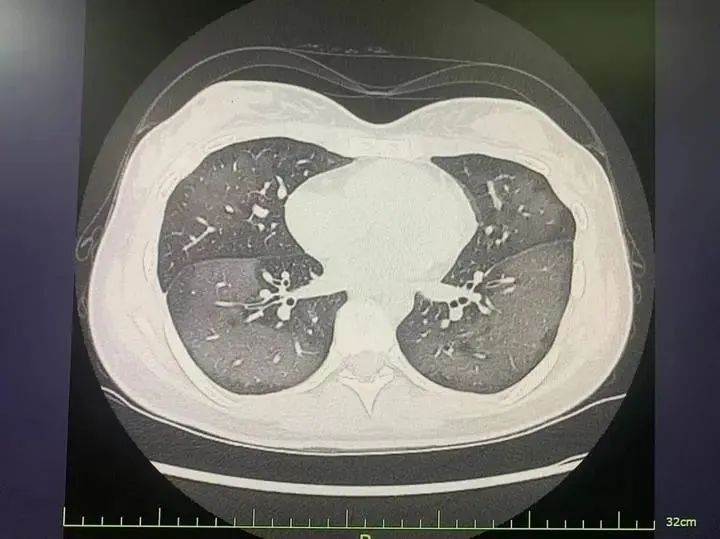

陳國(guó)慶副主任醫(yī)師接診后,迅速為涵涵安排了簡(jiǎn)單的血檢和胸片檢查,胸片結(jié)果提示兩肺大片斑片影,已接近“白肺”,血常規(guī)則提示白細(xì)胞升高、C反應(yīng)蛋白正常。

陳國(guó)慶了解了涵涵的病史并結(jié)合臨床表現(xiàn),基本考慮是防曬噴霧吸入后導(dǎo)致急性過(guò)敏性肺炎。

起病還不到一天,涵涵的胸片所提示的肺部病變?yōu)槭裁磿?huì)如此廣泛且彌漫?陳國(guó)慶說(shuō),“這是急性過(guò)敏性肺炎的典型表現(xiàn),來(lái)勢(shì)通常較為兇猛,如果不及時(shí)就診,可能會(huì)發(fā)展為重癥肺炎,出現(xiàn)呼吸衰竭等情況,危及生命。”